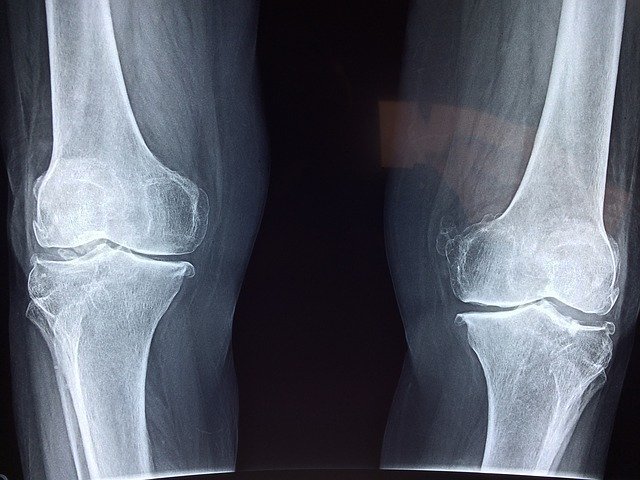

Your knee is a hinge joint with rotational capacity — a design that serves you well for walking and running but leaves you exposed under the torsional loads skiing generates. When you carve a turn, your lower leg rotates relative to your femur while your body weight is simultaneously multiplied by centrifugal force. The ACL resists anterior tibial displacement; the MCL resists valgus collapse. Both are tested hard on every aggressive turn at speed.

The menisci — the cartilage pads between your femur and tibia — absorb compressive load and distribute pressure across the joint surface. Repetitive impact without adequate recovery degrades meniscal tissue over years of accumulated vertical. Chronic meniscal stress is the quiet injury nobody discusses until an MRI makes it impossible to ignore. Understanding this anatomy tells you exactly where your preparation efforts need to focus.